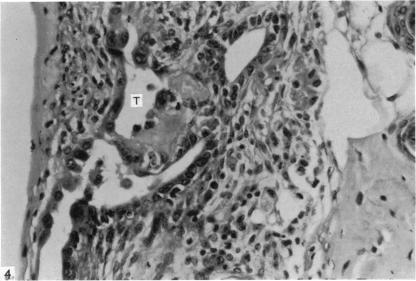

As a contribution to the problem of the immunological privilege of the fetus it was decided to investigate the fate of yolk sac grafts in mice. Ten-day post-coitum mouse visceral yolk sac was transplanted to a dermal tunnel in the flank of isogeneic animals. In this site the yolk sac was capable of surviving for at least 15 days past the normal duration of pregnancy. Yolk sac was transplanted to a similar site in allogeneic animals and was found to be destroyed by an immunological reaction within 13 days. Orthotopic skin grafts between the same strains of mice used in the yolk sac transplantation were rejected in first-set fashion within 13 days. A limited series of host animals, previously sensitized by visceral yolk sac, rejected orthotopic skin grafts in second-set fashion. These findings indicate that the cells of the visceral yolk sac in the mouse contain transplantation antigens. Possible reasons why such antigens do not lead to fetal rejection during pregnancy are considered.

为了研究胎儿免疫特权问题,决定对小鼠卵黄囊移植的命运进行研究。将受孕10天的小鼠内脏卵黄囊移植到同基因动物胁腹的皮肤隧道中。在此部位,卵黄囊能够在超过正常孕期的时间内存活至少15天。将卵黄囊移植到异基因动物的类似部位,发现其在13天内被免疫反应破坏。在卵黄囊移植中使用的相同品系小鼠之间的原位皮肤移植在13天内以初次排斥的方式被排斥。一系列有限的先前经内脏卵黄囊致敏的宿主动物以二次排斥的方式排斥原位皮肤移植。这些发现表明,小鼠内脏卵黄囊的细胞含有移植抗原。文中还考虑了此类抗原在孕期为何不会导致胎儿被排斥的可能原因。